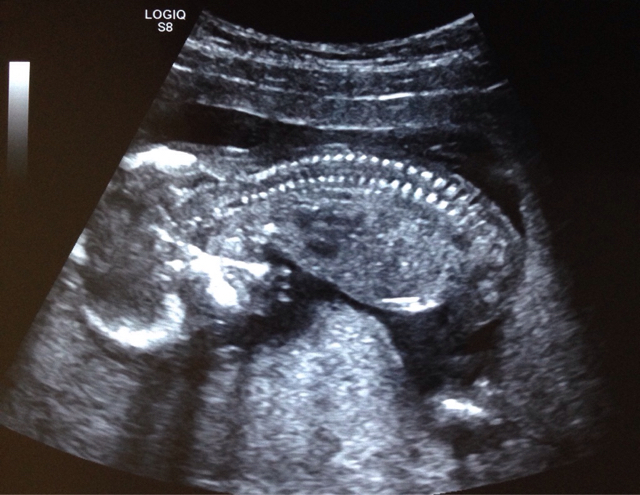

I'm thinking girl but not clear.

I dont think there are clues here. Lots going on in the pic